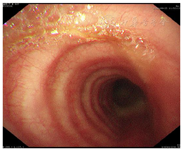

气管、左右主支气管及所属支气管黏膜稍充血,管腔内可见较多黏稠脓性分泌物(图2),清理后见各管腔通畅。于右下叶留取灌洗液送检细菌培养、真菌、结核、病毒及病原体NGS。转入呼吸ICU后,患者呼吸困难进一步加重(更换为高流量吸氧)、意识障碍无好转,病程中检验结果变化见表1,表2。